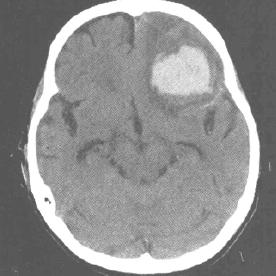

光敏性癫痫简称PSE,医学研究表明,部分人大脑可能存在潜在病变,对光线极为敏感,当他们长时间暴露在特定频率的闪光、快速变化的图像或强烈光影对比度变化等视觉刺激下,大脑神经元会异常放电,引发癫痫,症状轻时会头晕恶心、眼球上翻、意识丧失、肌肉抽动,严重时可能危及生命。